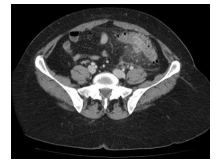

Gastroenterologia

Homem 66 anos, dor em abdome inferior e febre. Leuco – 17.100. Analisando a TC de abdome abaixo, podemos identificar

Diverticulite.